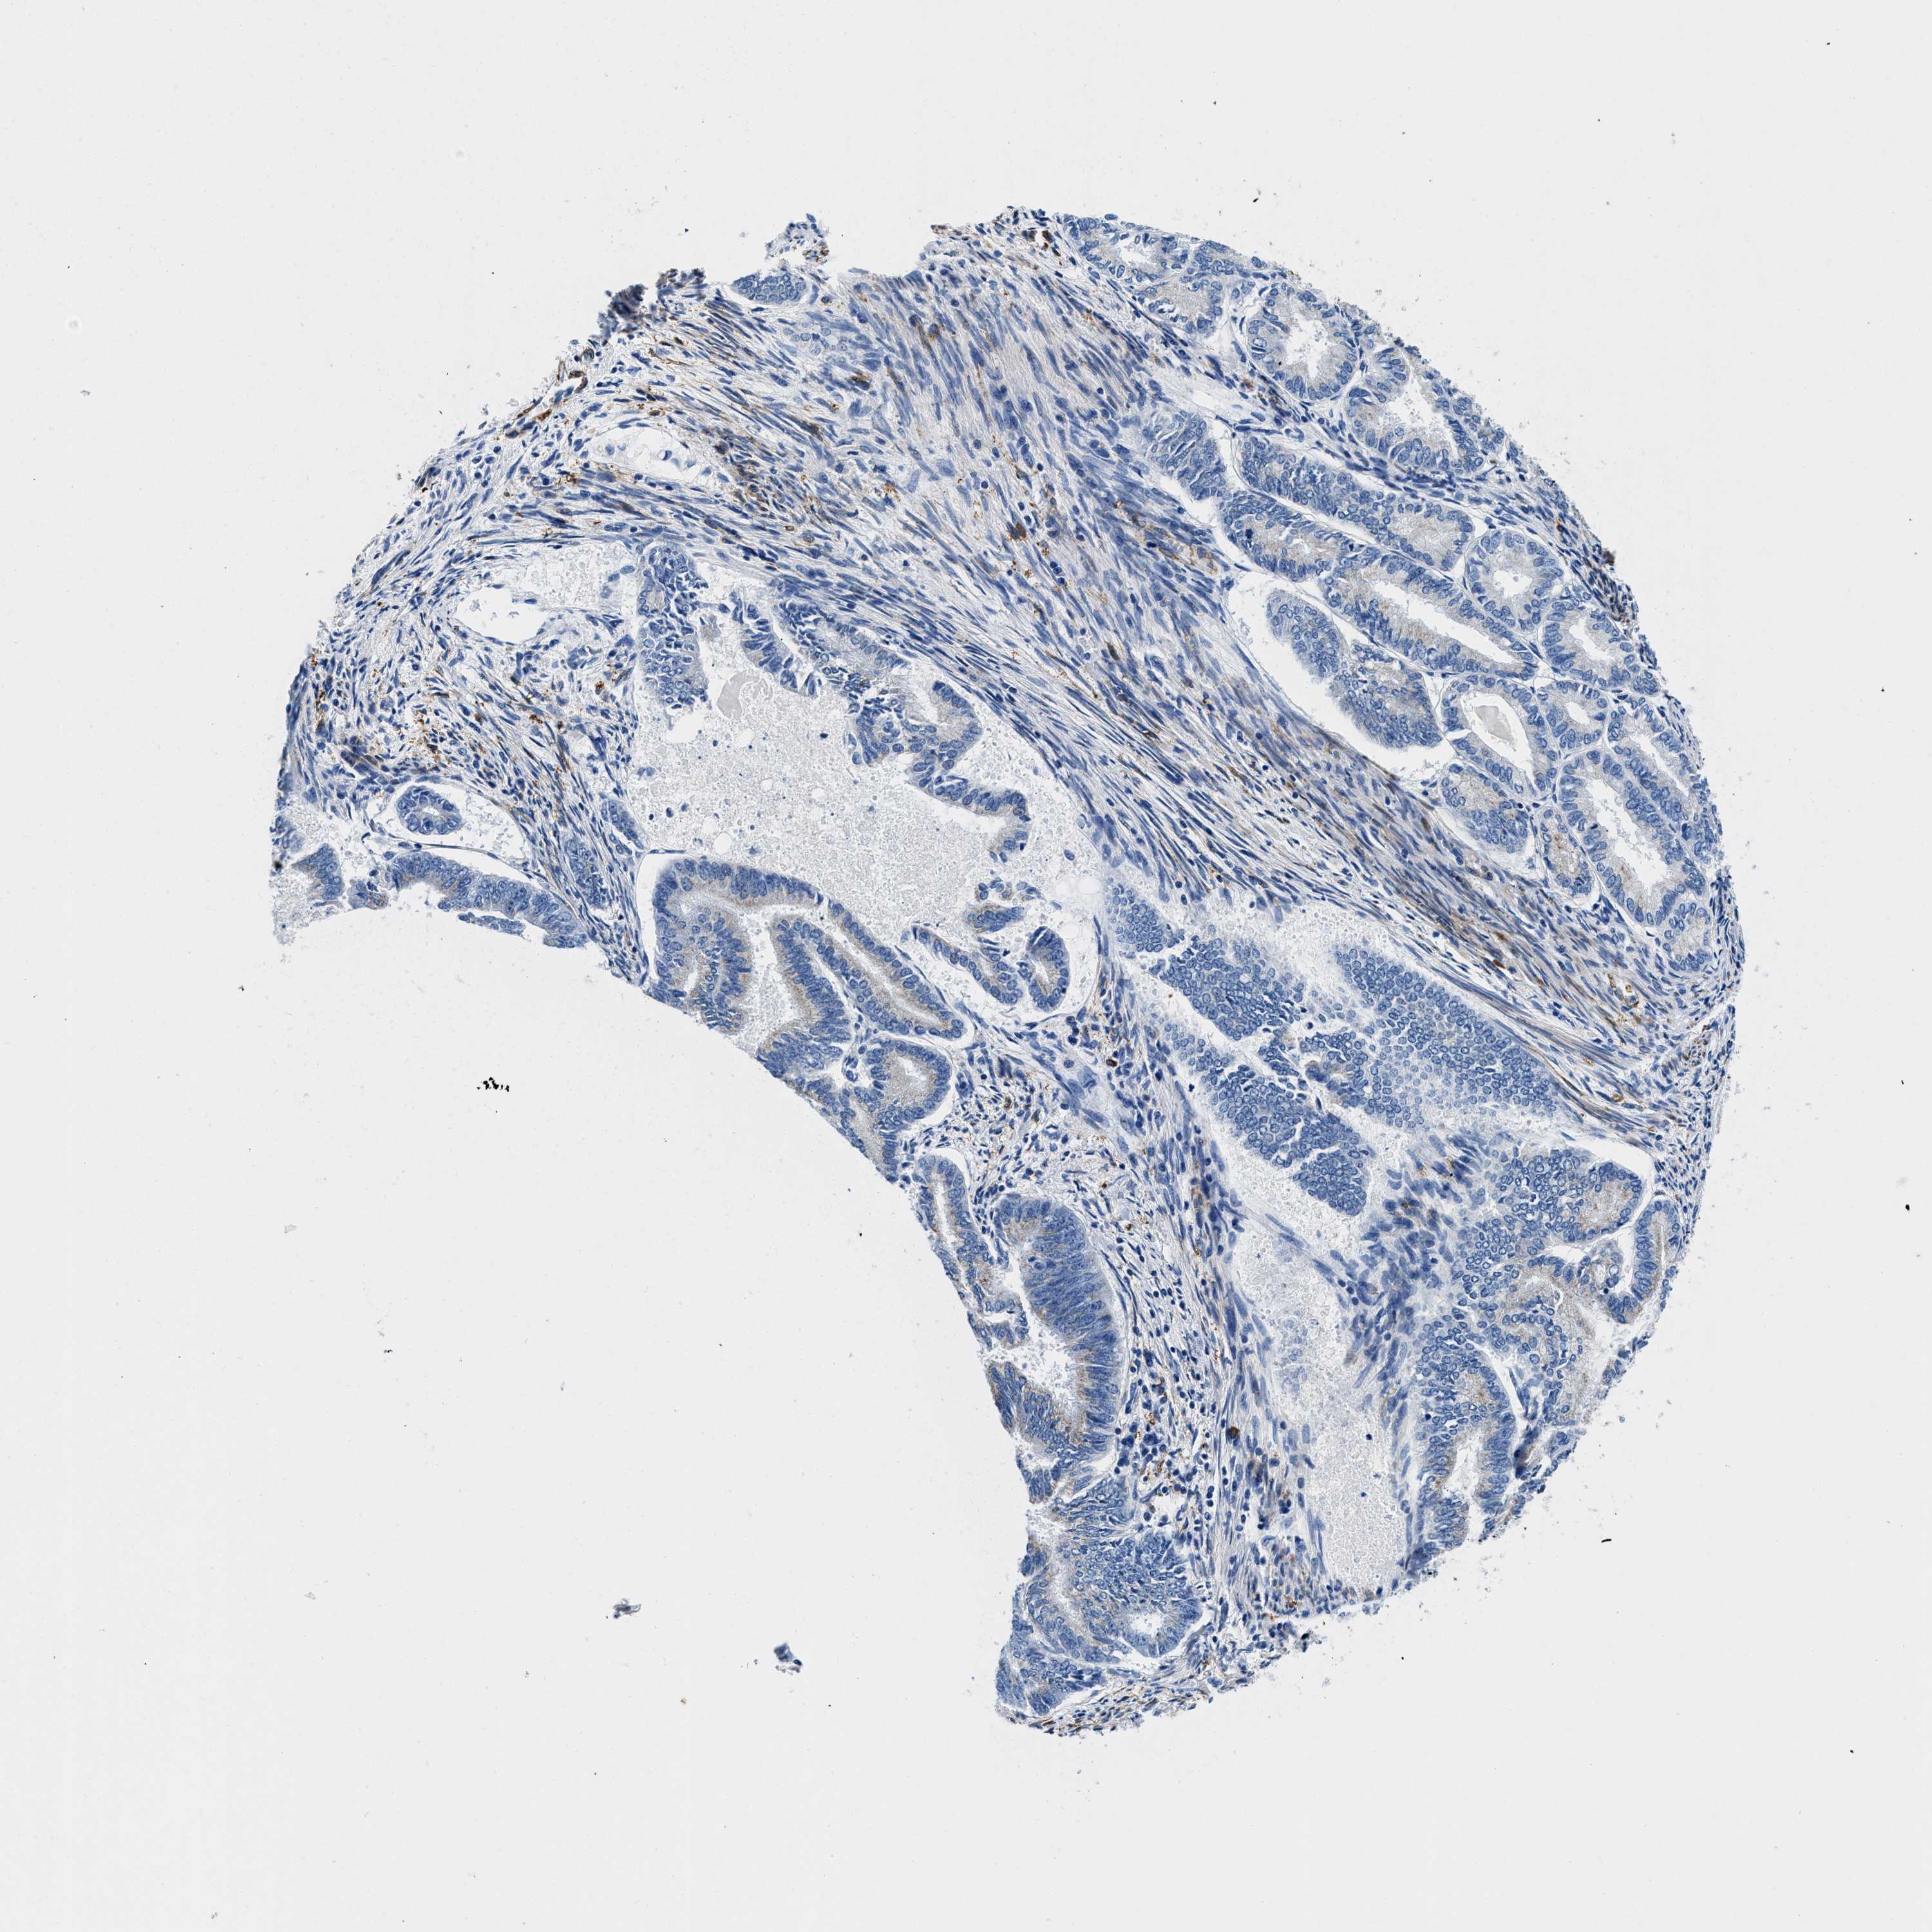

ENDOMETRIAL CANCER - Protein expressioni

A mouse-over function shows sample information and annotation data. Click on an image to view it in a full screen mode. Samples can be filtered based on level of antibody staining by selecting one or several of the following categories: high, medium, low and not detected. The assay and annotation is described here.

Note that samples used for immunohistochemistry by the Human Protein Atlas do not correspond to samples in the TCGA dataset.

Antibody stainingi

Antibody staining in the annotated cell types in the current human tissue is reported as not detected, low, medium, or high, based on conventional immunohistochemistry profiling in selected tissues. This score is based on the combination of the staining intensity and fraction of stained cells.

Each image is clickable and will lead to virtual microscopy that enables deeper exploration of all samples and also displays staining intensity scores, fraction scores and subcellular localization as well as patient and tissue information for each sample.

Antibody HPA016631

Staining

High

Medium

Low

Not detected

Intensity

Strong

Moderate

Weak

Negative

Quantity

>75%

75%-25%

<25%

None

Location

Nuclear

Cytoplasmic/membranous

Cytoplasmic/membranous,nuclear

Adenocarcinoma, NOS